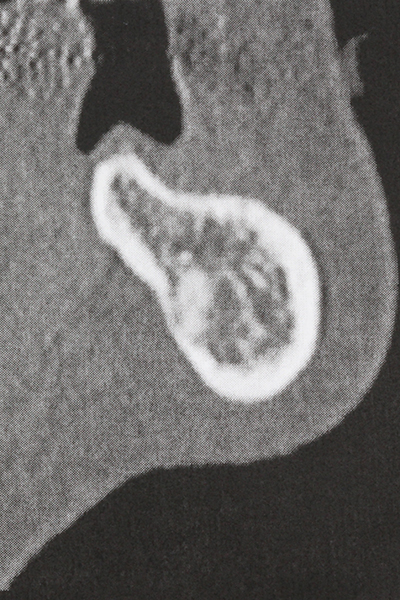

La preparazione della finestra laterale durante un rialzo del pavimento sinusale esterno è complicata, in particolare per gli implantologi con poca esperienza chirurgica. La rimozione della copertura ossea del seno senza danneggiare la membrana schneideriana sottostante è solo una parte dell'operazione: dopo aver stabilito un accesso adeguato, la membrana interna del seno deve essere spostata con cautela per far spazio ai materiali di accrescimento o agli impianti. La piezochirurgia è utile per questa indicazione in due modi: è possibile utilizzare gli strumenti diamantati per l'ablazione selettiva dell'osso e, se la procedura viene eseguita con precisione, la membrana mucosa sottostante rimane intatta. Le frequenze ultrasoniche permettono anche la separazione della membrana mucosa senza complicanze: le frequenze vengono trasmesse nello spazio compreso tra la membrana mucosa e il pavimento sinusale mediante degli speciali raccordi smussati (Cassetta, Ricci et al. 2012, Pereira, Gealh et al. 2014) (Rickert, Vissink et al. 2013). Di conseguenza, non sorprende che le rivisitazioni attuali del rialzo del pavimento sinusale esterno valutino positivamente l'utilizzo dei dispositivi piezoelettrici, delle superfici non lisce degli impianti e dei materiali di riempimento dell'osso (Wallace, Tarnow et al. 2012).

Esistono ulteriori applicazioni nella chirurgia sinusale. È possibile rimuovere patogeni e corpi estranei dal seno dopo la preparazione concentrica di una copertura ossea generalmente di forma trapezoidale nella parete anteriore del seno. La copertura ossea viene riposizionata al termine della fase operatoria nella zona intra-antrale e fissata con cunei o suture adattive per prevenirne il distacco.